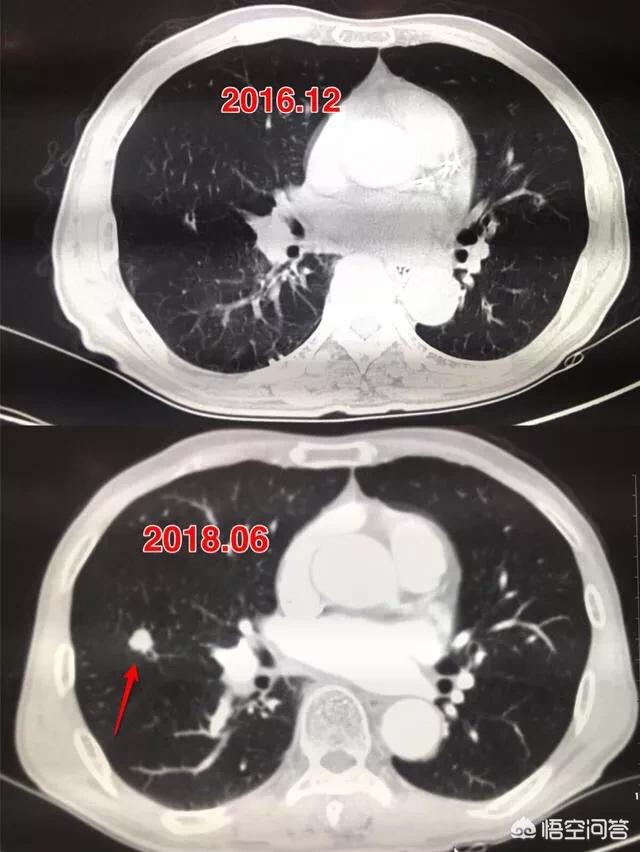

La flèche pointe vers le nodule, qui était très petit lorsqu'il a été découvert en mars 2016, environ 0,5 cm, et maintenant les examens médicaux de routine révèlent de très nombreux nodules comme celui-ci.Il n'existe aucun moyen de déterminer s'il s'agit d'une tumeur bénigne ou maligne sur les images, seule l'option de l'examen, et l'examen et le suivi constituent également le meilleur outil.

Sept mois plus tard, lors du deuxième examen de suivi en octobre 2016, il était évident que ce nodule était devenu plus grand et plus rond. Le nodule élargi lors du suivi devait alerter sur la possibilité d'une tumeur maligne, mais cette patiente n'a toujours pas opté pour la chirurgie.

Après encore 1 an et 2 mois, le troisième examen en décembre 2017.Vous pouvez voir que ce nodule est beaucoup plus grand qu'avant, les signes malins sont lobulés et il est devenu solide à l'intérieur, ces signes diagnostiquent le cancer du poumon fondamentalement, mais le patient n'a toujours pas été opéré.

Le nodule s'était transformé en masse (>3cm) et ce cancer du poumon pouvait être un cas d'école, avec fondamentalement tous les signes de malignité qui soutiennent le cancer du poumon.Bords irréguliers, lobulation, bavures et signes d'arrachement pleural.

Heureusement, aucune lésion métastatique n'a encore été observée et l'ablation chirurgicale est encore possible. Si le traitement n'est pas encore une option, revenez pour un examen dans un an et vous pouvez vous attendre à de multiples changements métastatiques. En fait, lors du deuxième examen, les lésions étaient plus importantes et une résection chirurgicale aurait dû être effectuée à ce moment-là, sans récidive ni métastase. À mesure que la lésion grossit, il peut y avoir des cellules cancéreuses dans le sang, et le risque de récidive et de métastase est alors plus élevé.